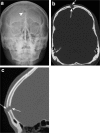

Calvarial lesions are often asymptomatic and are usually discovered incidentally during computed tomography or magnetic resonance imaging of the brain. Calvarial lesions can be benign or malignant. Although the majority of skull lesions are benign, it is important to be familiar with their imaging characteristics and to recognise those with malignant features where more aggressive management is needed. Clinical information such as the age of the patient, as well as the patient's history is fundamental in making the correct diagnosis. In this article, we will review the imaging features of both common and uncommon calvarial lesions, as well as mimics of these lesions found in clinical practice. TEACHING POINTS: • Skull lesions are usually discovered incidentally; they can be benign or malignant. • Metastases are the most frequent cause of skull lesions. • Metastatic lesions are most commonly due to breast cancer in adults and neuroblastoma in children. • Multiple myeloma presents as the classic "punched out" lytic lesions on radiographs. • Eosinophilic granuloma is an osteolytic lesion with bevelled edges.